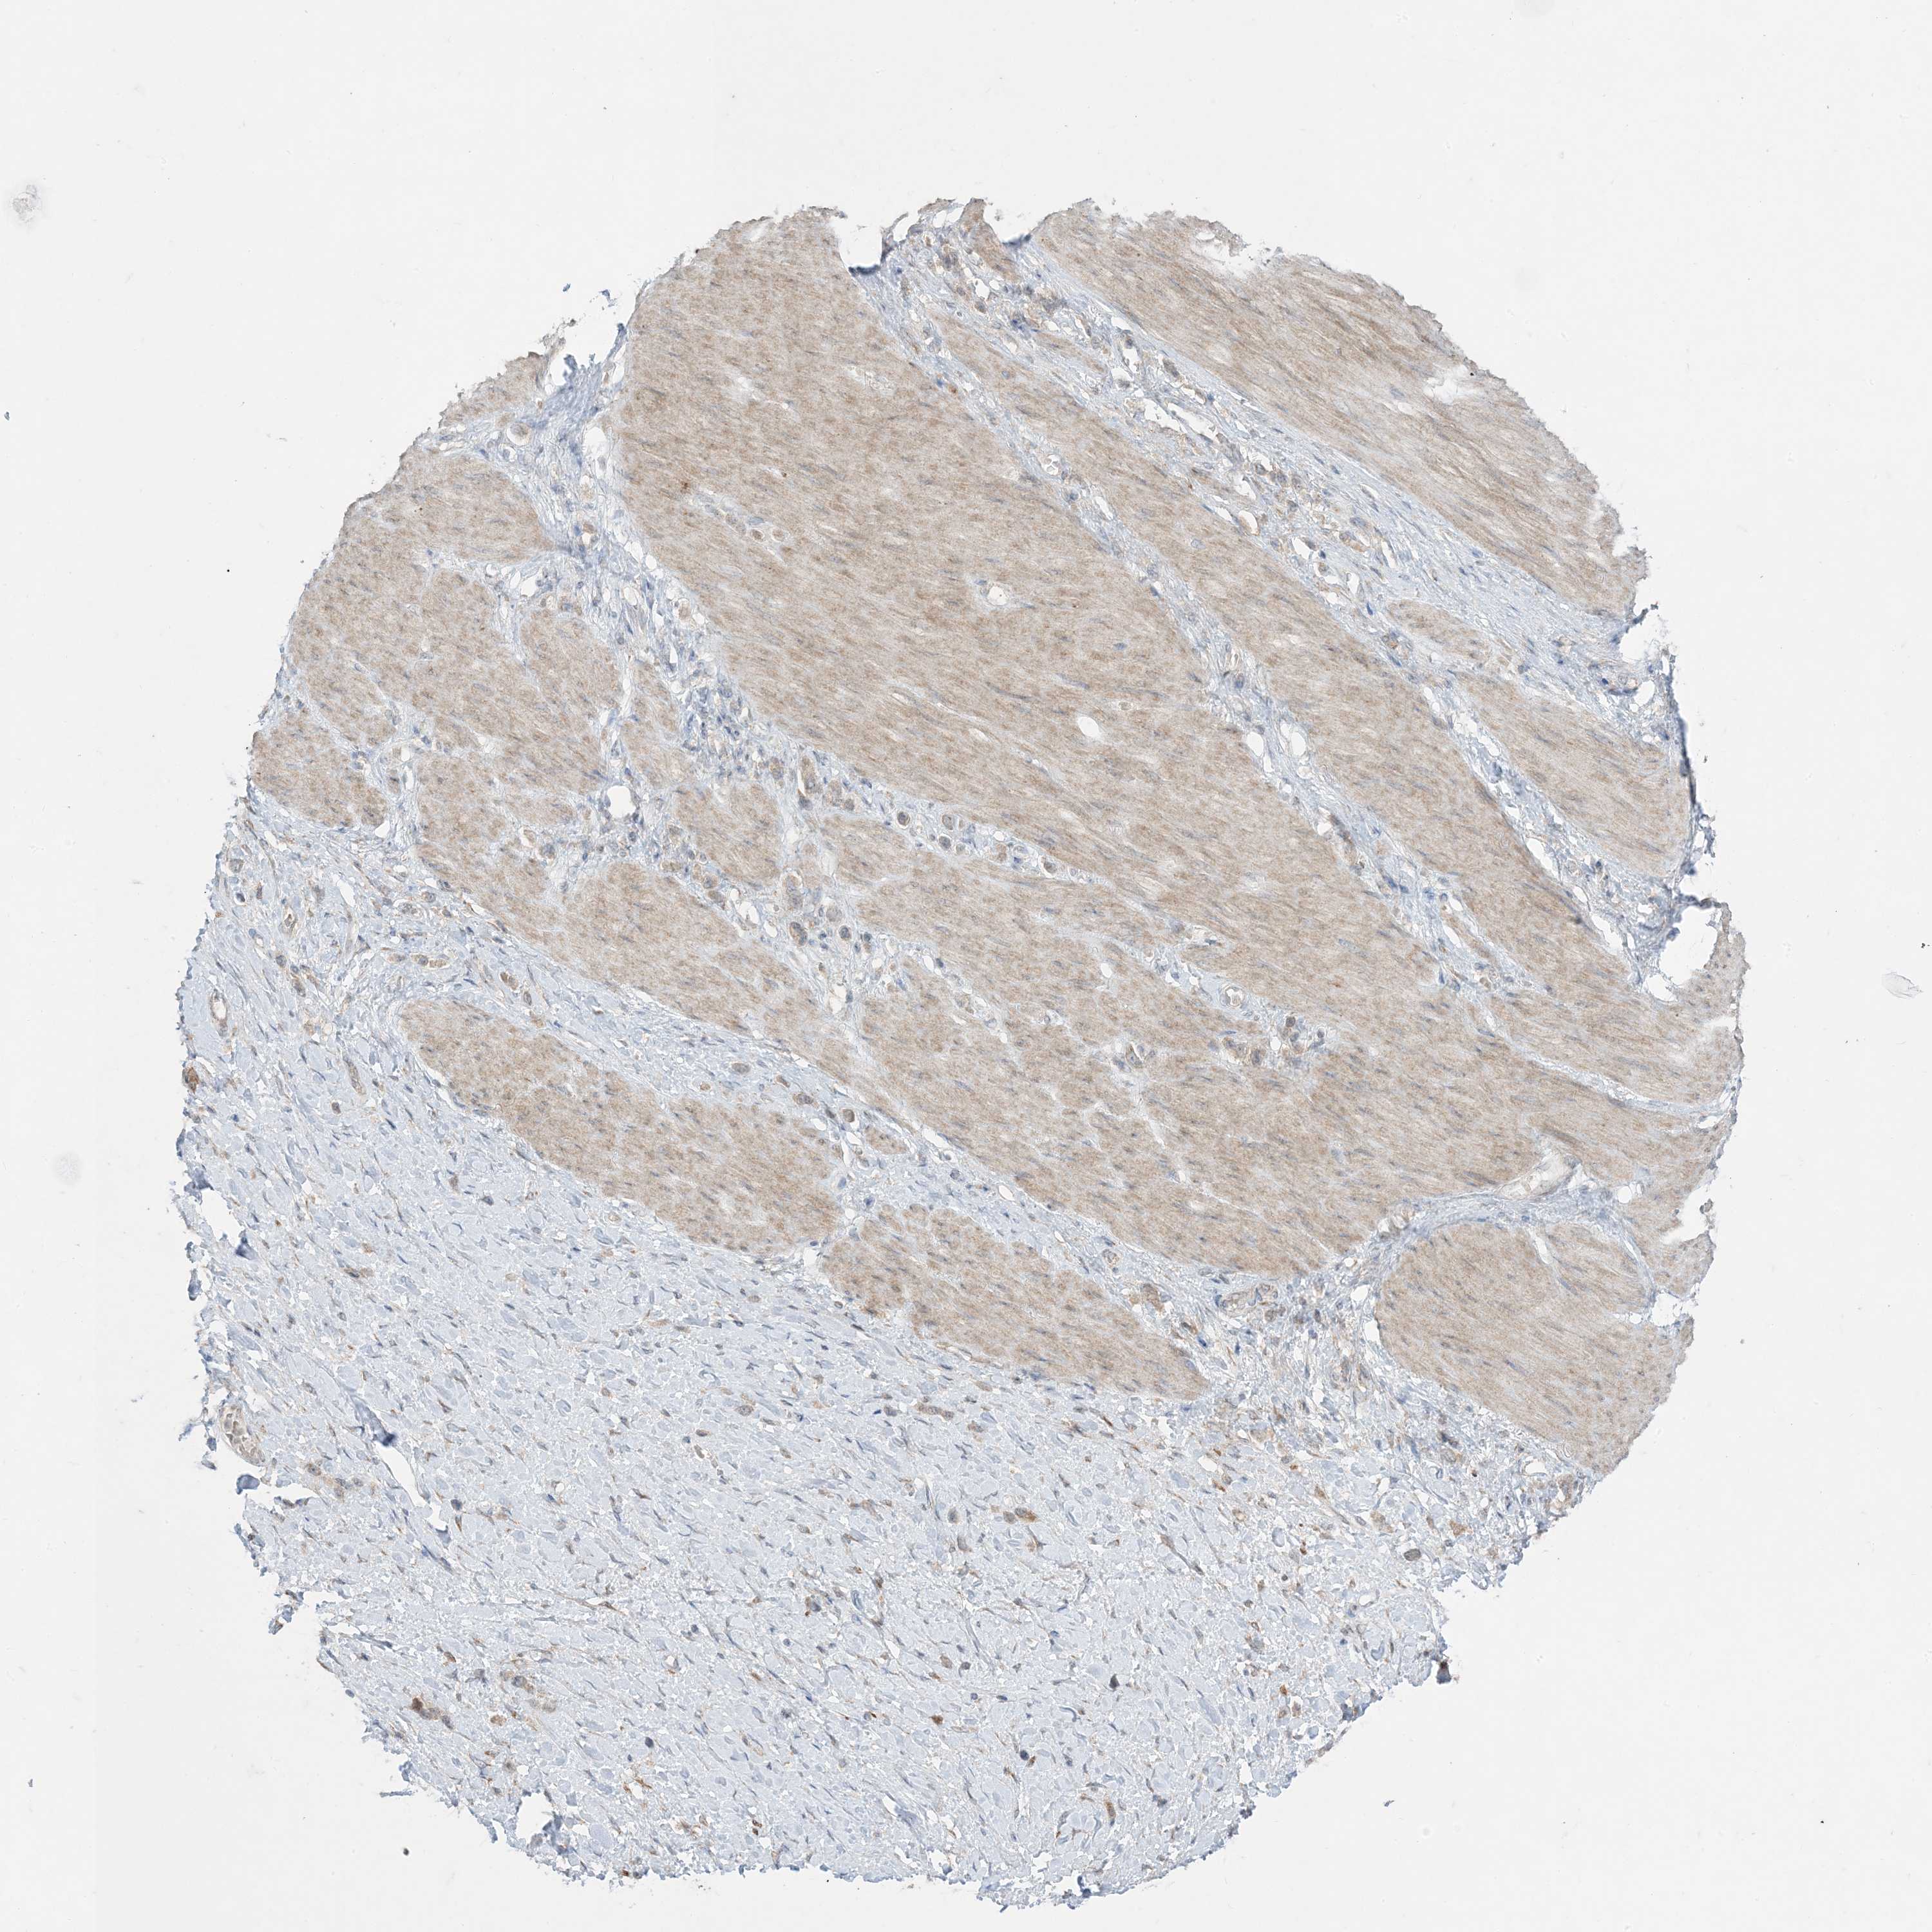

STOMACH CANCER - Protein expressioni

A mouse-over function shows sample information and annotation data. Click on an image to view it in a full screen mode. Samples can be filtered based on level of antibody staining by selecting one or several of the following categories: high, medium, low and not detected. The assay and annotation is described here.

Note that samples used for immunohistochemistry by the Human Protein Atlas do not correspond to samples in the TCGA dataset.

Antibody stainingi

Antibody staining in the annotated cell types in the current human tissue is reported as not detected, low, medium, or high, based on conventional immunohistochemistry profiling in selected tissues. This score is based on the combination of the staining intensity and fraction of stained cells.

Each image is clickable and will lead to virtual microscopy that enables deeper exploration of all samples and also displays staining intensity scores, fraction scores and subcellular localization as well as patient and tissue information for each sample.

Antibody HPA001536

Antibody CAB035996

Staining

High

Medium

Low

Not detected

Intensity

Strong

Moderate

Weak

Negative

Quantity

>75%

75%-25%

<25%

None

Location

Nuclear

Cytoplasmic/membranous

Cytoplasmic/membranous,nuclear

Adenocarcinoma, NOS

Adenocarcinoma, High grade